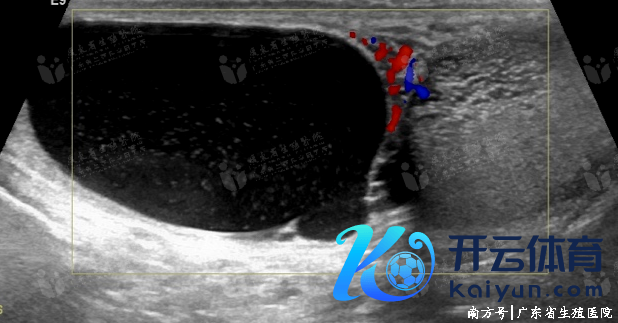

较荒芜,多因炎症、结核、外伤导致睾丸网或睾丸输出小管梗阻所致,也可见于先天性发育不良,如睾丸网和输出小管发育不良等。睾丸生精功能遍及但附睾内莫得精子。声像图上睾丸大小、方式经常遍及,睾丸纵隔处睾丸网呈不同进度敷裕性细网状彭胀,梗阻严重者,睾丸网相近精直小管亦可见不同进度彭胀。先天性睾丸网梗阻时,附睾回声多无彰着特别。外压等后天性成分导致梗阻时,在附睾头区域可见重大囊肿。

睾丸网先天性梗阻

附睾头囊肿压迫所致睾丸内梗阻